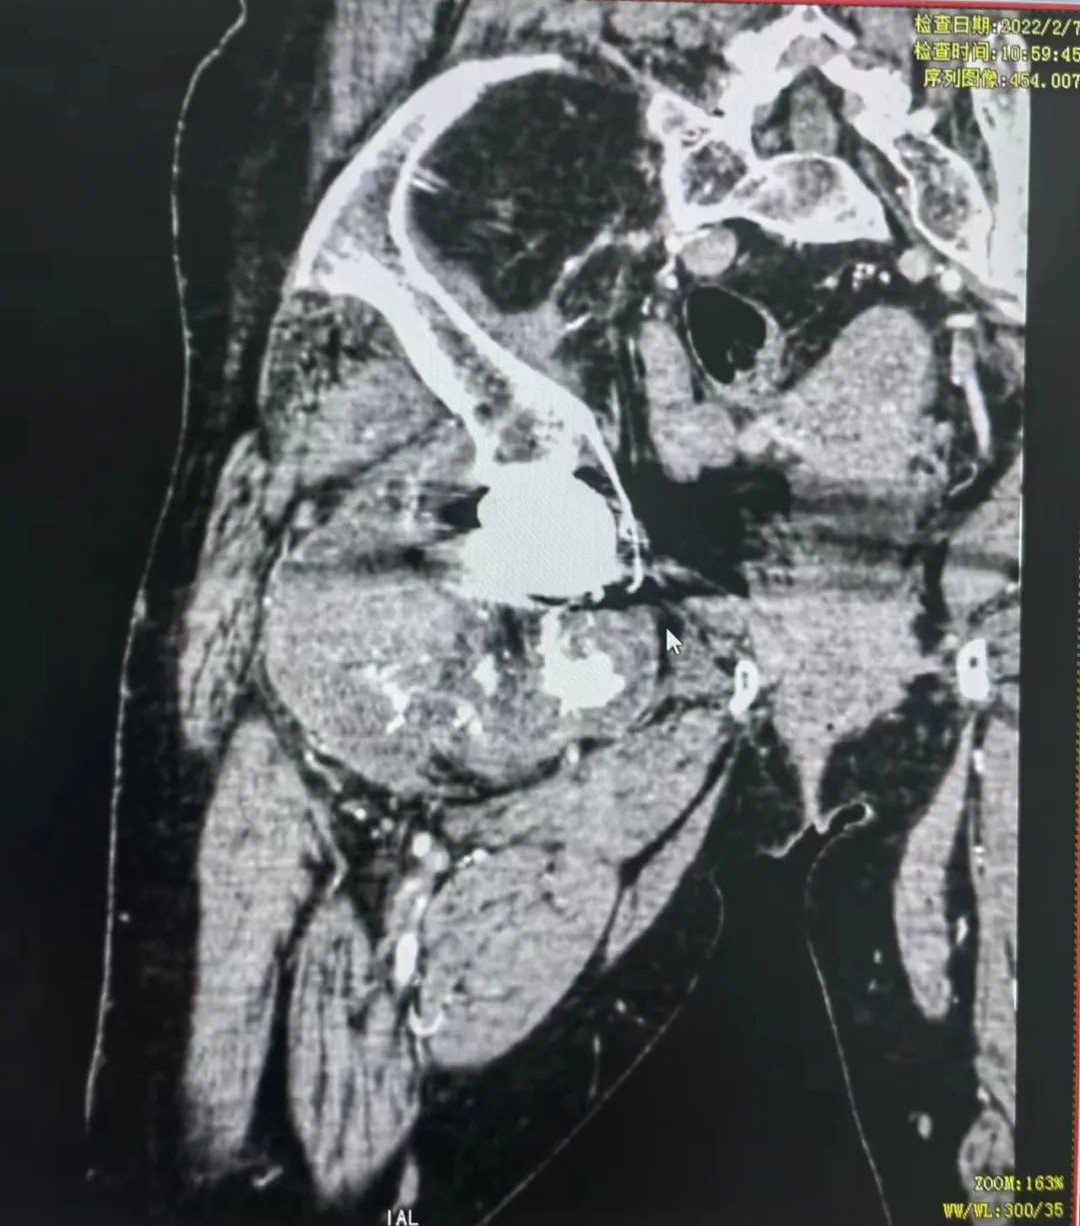

今年59岁的张阿姨,四年前就因为患上了良性肿瘤置换了右髋关节。2021年底,张阿姨右髋部又长出了一个大包块,按之有疼痛感,起初张阿姨并没有在意,后来越来越严重。到当地医院检查发现,张阿姨是考虑恶性肿瘤(软骨肉瘤)复发,肿瘤从胯部的髋关节处一直延伸至大腿的股骨处,约为24厘米长,当地医院建议到省城医院看看。

张阿姨的肿瘤从胯部的髋关节处一直延伸至大腿的股骨处

辗转省城多家医院,都被告知要“截肢”,而且须截除半骨盆。原来,复发的肿瘤不仅破坏了股骨近段,包绕了原来的关节,而且造成同侧骨盆受累,为了最大程度将肿瘤切除干净,手术就须切除半骨盆及同侧髋关节。如果保肢,就要在原本难度颇高的髋关节复发病灶扩大切除术的基础上进行半骨盆置换,手术难度和危险系统都呈几何倍数增加,对于医院和医生来讲都是个很大的挑战。

“患者的病灶范围很大,从盆骨向下生长侵袭股骨经过髋关节,直到骨盆,要想完全清除病灶,手术必须要在髋关节外进行,完整切除骨盆及股骨上段病灶,因为如果打开关节,肿瘤切碎后形成肿瘤细胞会脱落于体内,引起新一轮的复发。当时患者病灶已经突破骨皮质,侵及软组织常规的关节内切除无法达到肿瘤外科的手术切除边界要求,同时重建骨盆及股骨,所以手术难度相对还是挺大的。”谈起这场手术的难度,张兵到现在还记忆如新。切除只是手术的第一步,更重要的是要帮助患者精准地重建还原生理结构,保障其后的生活质量。“我们利用3D打印技术,为患者订制了两个个体化的髋关节假体,假体大小结构精确到毫米,使假体可与患者精准契合,最大化重建和恢复其身体的力学结构。”近几年来,张兵团队利用3D打印技术,帮助了无数患者恢复正常生活。